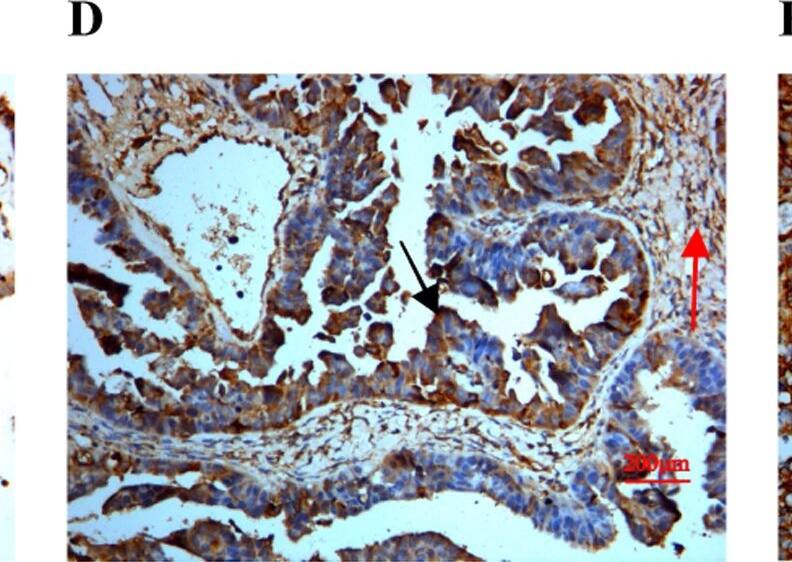

SPARC/Osteonectin antibody in Human Ovary by Immunohistochemistry (IHC-P).

SPARC/Osteonectin in Human Ovary.

SPARC/Osteonectin was detected in immersion fixed paraffin-embedded sections of human ovary using Goat Anti-Human SPARC/Osteonectin Antigen Affinity-purified Polyclonal Antibody (Catalog # AF941) at 3 µg/mL overnight at 4 °C. Tissue was stained using the Anti-Goat HRP-DAB Cell & Tissue Staining Kit (brown; CTS008) and counterstained with hematoxylin (blue). View our protocol for Chromogenic IHC Staining of Paraffin-embedded Tissue Sections.